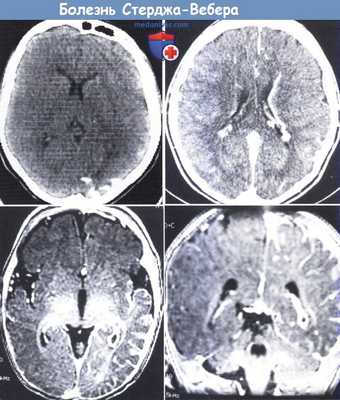

(а) На рисунке коронального среза определяются определяется распространенный пиальный ангиоматоз. Изменения окружают пораженные извилины. Визуализируются расширенные глубокие венозные коллатерали, по которым венозная кровь шунтируется в глубокую венозную систему. Кроме того, отмечается увеличение размеров сосудистого сплетения и атрофия правого большого полушария головного мозга.

(б) МРТ, постконтрастное Т1-ВИ, корональный срез: определяются протяженное контрастирование «серпантинного» характера утолщенной мягкой мозговой оболочки (пиальный ангиоматоз) и увеличение субарахноидального пространства над правым большим полушарием головного мозга. Очевидна выраженная правосторонняя гемиатрофия головного мозга. (а) МРТ, постконтрастное Т1-ВИ, аксиальный срез: определяется классический синдром Стерджа-Вебера (ССВ) в виде атрофии правого большого полушария, увеличения размеров ипсилатерального сосудистого сплетения и распространенного пиального ангиоматоза, покрывающего практически всю поверхность полушария.

(б) МРТ, постконтрастное Т1-ВИ, более краниальный аксиальный срез: у того же пациента определяются схожие изменения. На данном изображении в субарахноидальном пространстве визуализируется скопление расширенных сосудов.

Синдром Стерджа-Вебера.

Слева сверху: на КТ видны типичные кальцинаты в затылочной области.

Справа сверху: аномальное распространение вен вдоль угла желудочка.

Снизу: МРТ с контрастированием гадолинием выявило захват контраста в области ангиомы мягкой сосудистой оболочки в задней части левого полушария (слева—аксиальная проекция, справа— фронтальная проекция).

Заметно расширение сплетения сосудистой оболочки левого глаза и распространение вен в переднем сагиттальном синусе.